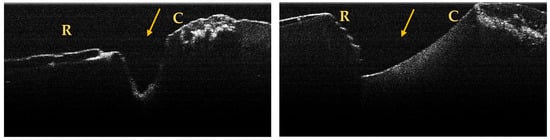

A maximum of 512 OCT images was taken for each dental surface examined. Figure 3, Figure 4 and Figure 5 present specific OCT images of teeth with macroscopically identified NCCLs, but also specific OCT images of teeth in which the NCCLs were not visible macroscopically. In each figure depicting the OCT images obtained, the position of the dental crown is marked with the letter C, the position of the root is marked with the letter R, and the arrow indicates the NCCL.

OCT images of a saucer-shaped NCCL, indicated by the arrows.

Figure 5.

OCT images of an irregular NCCL, indicated by the arrows.